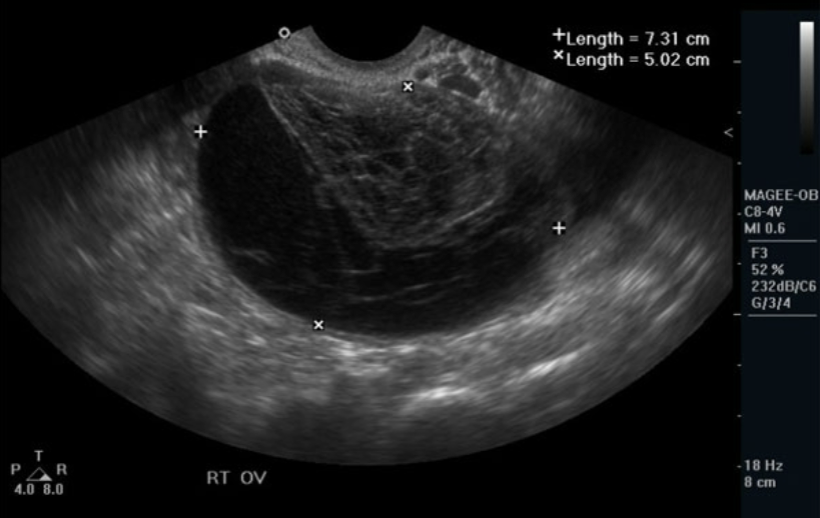

Mucinous Cystadenoma

Contains thicker, mucinous fluid

More frequent chance of malignancy

Usually multi-locular

VERY LARGE! ( may reach up to 30 cm)

multiple septations

may contain debris

bilateral in <5% of cases